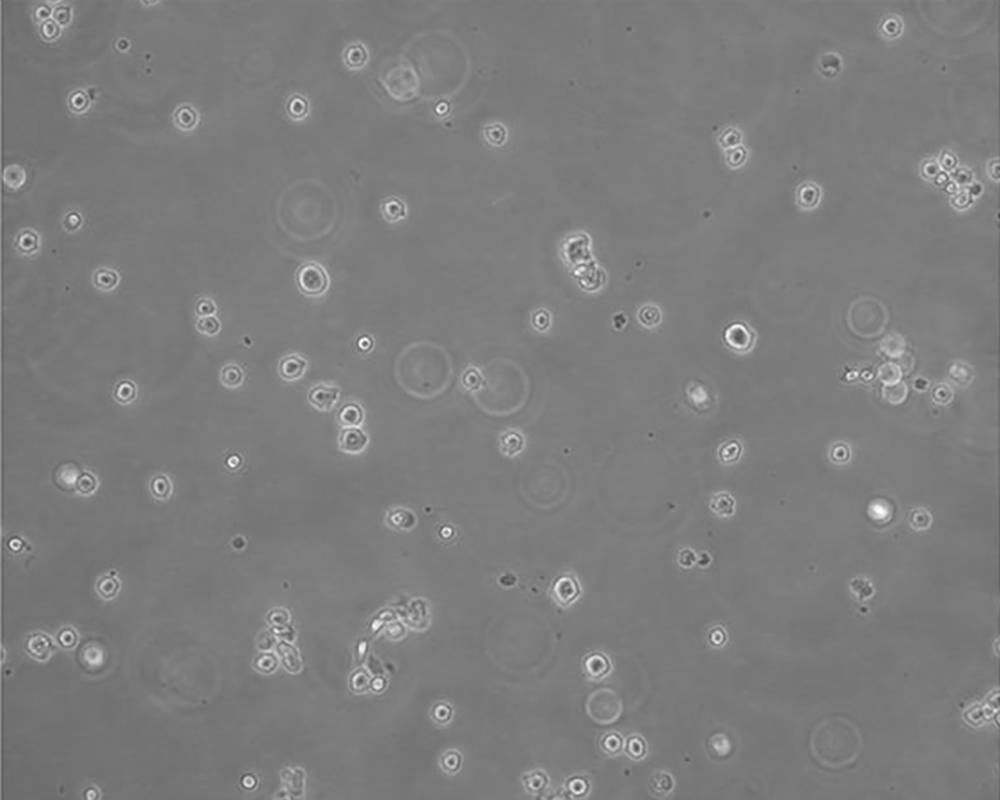

生長特性 suspension

形態(tài)特征 lymphoblast

細(xì)胞描述 該細(xì)胞來源于多發(fā)性骨髓瘤男性患者,表達(dá)IgG,分泌IL-6。